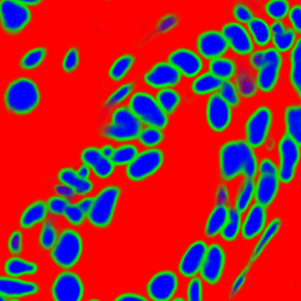

The task of nuclei segmentation can be roughly divided into two stages: the first stage is extracting the foreground(nuclei), the second stage is segmenting the connected foreground area into separated nuclei and finding out the boundary of each nucleus. Our method intends to merge these two steps by extracting the nuclei and their edges at the same time. That is the reason why it is named ”nuclei-boundary(NB) model”. As shown in Fig.3, the output of the NB model has three channels, each has the same height and width with the input image. Its values represent the probabilities of each pixel being , or class, respectively. The manual annotation for our segmentation problem is the boundary of each nucleus. A pixel belonging to the class means that it is on or inside an annotated boundary and within 2 pixel from the boundary. Pixels of the class are those that are inside annotated boundary but are not pixels. Correspondingly, the output can be regarded as an RGB image and the estimated maps of the , and are represented by red, green and blue, respectively, as shown in Fig.3. To generate the ternary mask for training, we apply a morphology operator to each nucleus to obtain the pixels, and then subtract pixels from the nucleus to get pixels.

Figure 6 shows how our method segments the nuclei step by step. The color variety is well controlled by the color normalization procedure. The prediction result shows clear nuclear areas and nucleus boundaries. In the final segmentation result and ground truth image, each nucleus is represented by a different color.